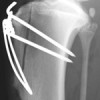

Patellar Luxation in Dogs

To understand why patellar luxation in dogs occurs, and how it can be treated, it is helpful to understand a little anatomy. The quadriceps muscle is the large muscle at the front of the thigh and is responsible for extending the stifle (knee) joint. The patella (kneecap) is a bone that is attached to the […]